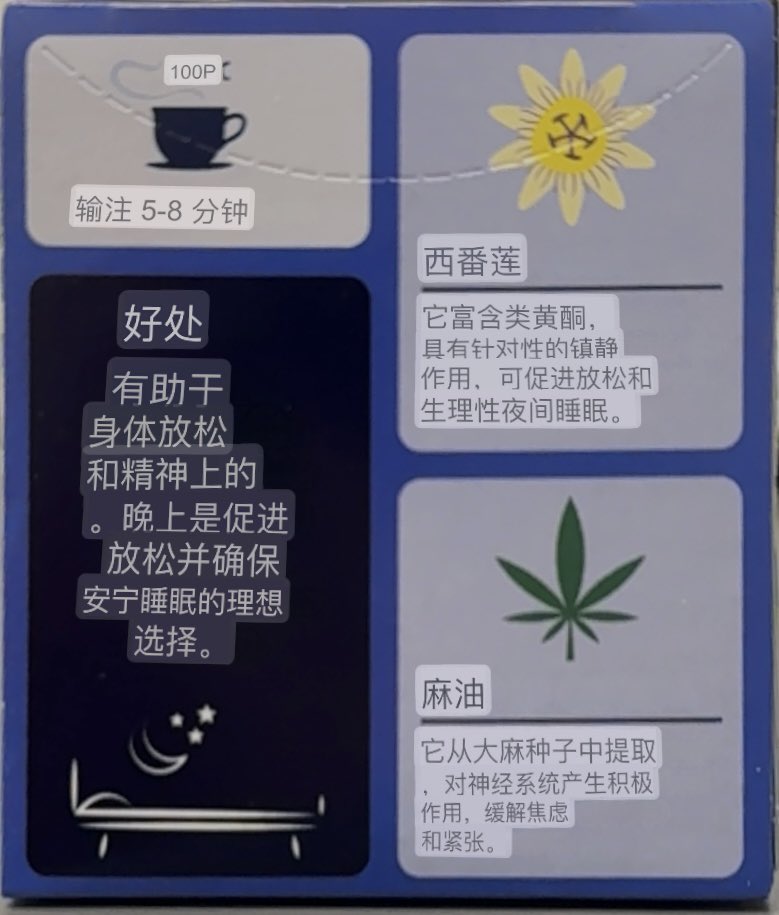

甚至在第二天有余晖的感觉,虽然发生了很多破事但没怎么影响心情*抗焦虑&镇静

运动协调性稍差,表现为走路和站立时平衡不好

此剂量下对睡眠的改善作用,增加了慢波睡眠且没有影响rem,精力恢复+

FDA数据,在临床剂量下(75-600mg)普瑞巴林的依赖性低于bzd,并相比之下它产生的认知和精神运动障碍较轻 https://t.co/TJ7ZOQ7pbC